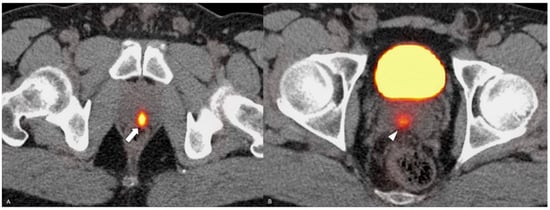

- Yang, J.; Xiao, L.; Gao, X.; Tang, Y.; Hu, S. Primary Adenosquamous Carcinoma of the Prostate With Multiple Heterogenic Metastases Demonstrated on 68Ga-PSMA and 18F-FDG PET/CT Imaging. Clin. Nucl. Med. 2024, 49, 180–181. [Google Scholar] [CrossRef] [PubMed]